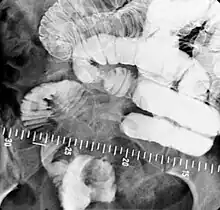

Small bowel follow-through

Indications to do this procedure are: unexplained chronic abdominal pain with weight loss, unexplained diarrhea, anemia which is caused by gastrointestinal bleeding or dependent on blood transfusion where the cause cannot be explained despite OGDS or colonoscopy investigations, partial obstruction of bowel/small bowel adhesive obstruction suspected, and unexplained malabsorption of nutrients.[13] For barium follow-through examinations, a 6-hour period of fasting is observed prior to the study.[10]

Barium is administered orally, sometimes mixed with diatrizoic acid (gastrografin) to reduce transit time in the bowel. Intravenous metoclopramide is sometimes also added to the mixture to enhance gastric emptying.[17] 600 ml of 0.5% methylcellulose can be given orally, after barium meal is given, to improve the images of small bowel follow-through by reducing the time taken for barium to pass through the small intestines, and increase the transparency of the contrast-filled small bowels.[18] Other methods to reduce transit time are to add ice cold normal saline after the administration of barium saline mixture[19] or to give a dry meal.[20]

X-ray images are then taken in a supine position at intervals of 20–30 minutes. Real-time fluoroscopy is used to assess bowel motility. The radiologist may press or palpate the abdomen during images to separate intestinal loops. The total time necessary for the test depends on the speed of bowel motility or transit time and may vary between 1 and 3 hours.[17]

- Barium follow-through examinations are the most commonly used imaging technique in assessing patients with Crohn's disease, although CT and magnetic resonance imaging are widely accepted as being superior.[1] However Barium examinations remain superior in the depiction of mucosal abnormalities.[24] The features of Crohn's disease are well described by barium follow-through examinations, appearing as a typical "cobblestone pattern", but no information is obtained regarding extraluminal disease.[28] Radiographic imaging in Crohn's disease provides clinicians with objective evaluations of small bowel regions that are not accessible to standard endoscopic techniques.[29] Because of its length and complex loops, the small intestine is the most difficult part of the gastrointestinal tract to evaluate. Most endoscopic techniques are limited to the examination of proximal or distal segments, hence Barium follow-through remains in most centres the test of choice for the investigation of abdominal pain, diarrhoea and in particular diseases manifesting mucosal abnormalities such as coeliac and Crohn's disease.[26]